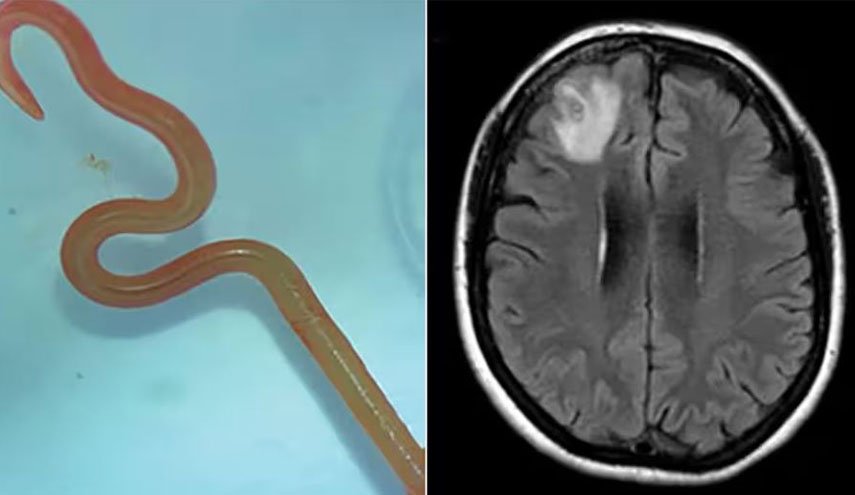

جراحة الأعصاب بيتسي غرونش أوضحت بعض أسباب هذا الداء وأعراضه لموقع "بز فييد" حيث قالت إن "ديدان الدماغ" هي طفيليات تصيب أجزاء من أجسامن.

وأضافت: "الأكثر شيوعًا دودة شريط لحم الخنزير، تينيا سوليوم (أو داء الكيسات العصبية)".

بحسب بيتسي فإن هذه الدودة لا يمكنها الانتقال إلى الدماغ لكن يرقاتها يمكنها ذلك، حيث تضع الدودة يرقاتها بمجرد دخولها للأمعاء مستخدمة أجسامنا كوسيط، وإذا لم يتم طرد البيض من أجسامنا من خلال البراز، فقد تنمو إلى يرقات.

يمكن لهذه اليرقات أن تنتقل إلى أعضاء أخرى من خلال مجرى الدم، قد تنتقل هذه الديدان الشريطية أيضا من إنسان إلى آخر إذا كان لدى الشخص عادات غير صحية مثل عدم غسل يديه جيدًا بعد استراحة الحمام.

وتابعت: "قد يستغرق ظهور أعراض عدوى الدماغ شهورا إلى سنوات، حيث لا تظهر الأعراض عادة إلا بعد موت اليرقات، وعندما تظهر في الدماغ، تشمل الأعراض الغثيان والنوبات والصداع".